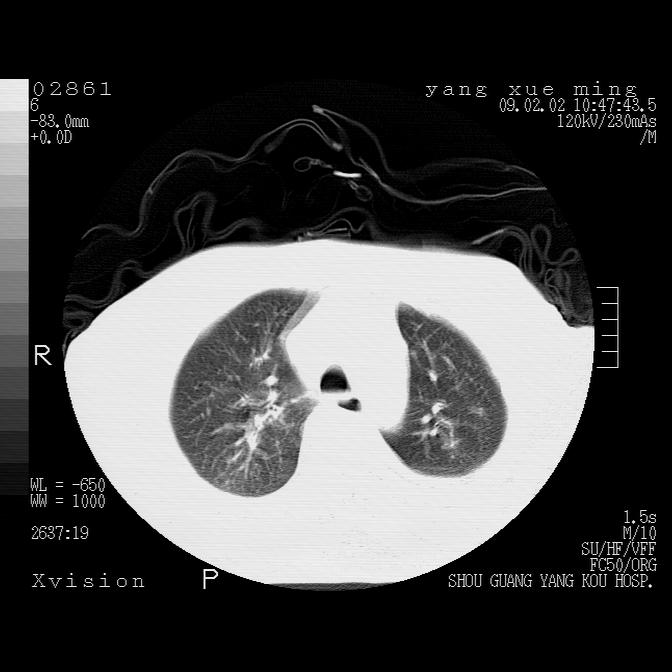

以下是引用lkc8963在2009-2-3 20:11:00的发言:[br]1)右上肺陈旧病灶。2)右下肺团块及团片影,影像表现符合感染。3)左心增大,左冠脉钙化,符合冠心病。4)双侧肺门扩大,以左侧为著,肺动脉干略粗,左上肺局限性气肿,为谨慎起见,需除肿瘤,建议增强。

以下是引用王仕学在2009-2-3 20:28:00的发言:[br]考虑右下肺感染,建议治疗后复查。